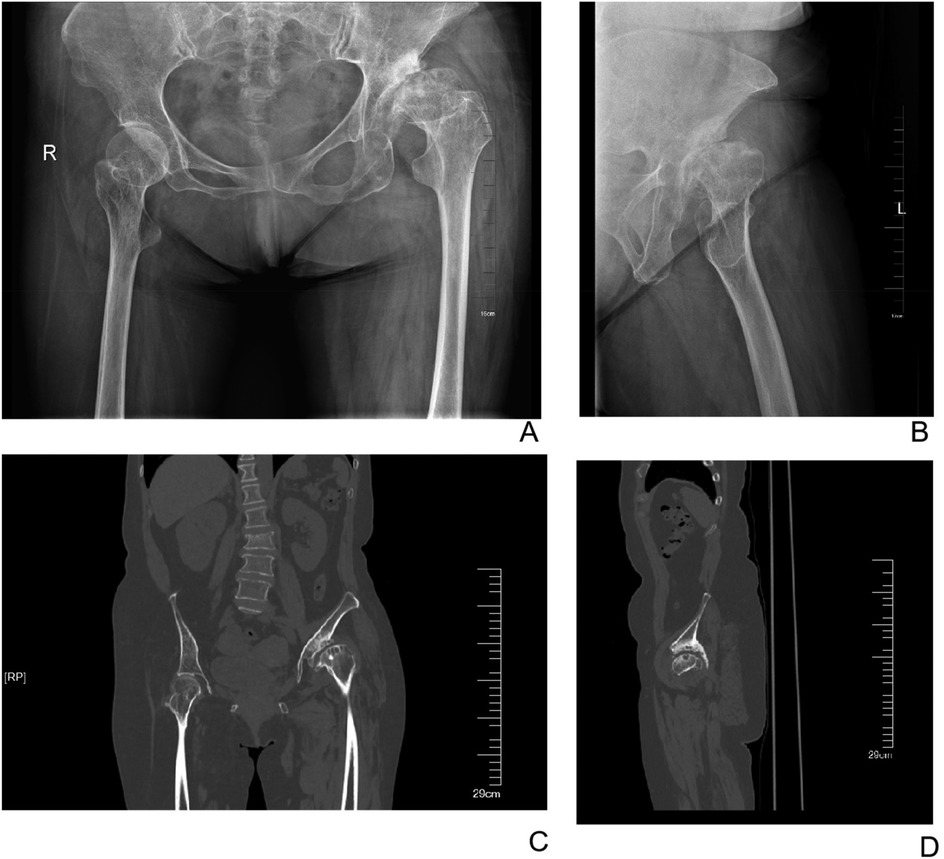

The patients were followed up for a mean duration of 2.17 ± 0.23 years. The LLD decreased from 22.13 ± 11.22 mm before surgery to 4.27 ± 2.15 mm after surgery (P < 0.001). Furthermore, the vertical distance of the hip rotation center decreased from 41.14 ± 12.17 mm before surgery to 20.76 ± 9.91 mm after surgery (P < 0.001), while the horizontal distance of the hip rotation center decreased from 40.20 ± 13.33 mm before surgery to 22.61 ± 6.88 mm after surgery (P < 0.001). Moreover, the mean healing time for the grafted bone in-growth was 7.65 ± 4.19 months (Figures 2, 3). Finally, the HHS score improved from 43.75 ± 12.67 points preoperatively to 90.15 ± 8.91 points at the last follow-up (P < 0.001) (Table 2).

Figure 2. Preoperative X-ray and CT images of a 60-year-old female patient. (A) Anteroposterior radiograph of the hips. (B) Lateral radiograph of the left hip. (C) Anteroposterior CT image of the hips. (D) Lateral CT image of the left hip.